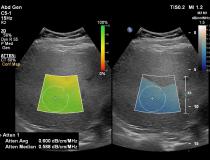

Philips Healthcare Epiq Ultrasound GI Liver

-

The Philips liver fat quantification tool.